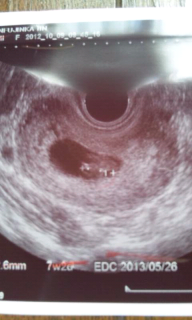

前回流産しているので一週間ぶりに受診。 先週も心臓ピコピコで今回もピコピコ♩ へその緒や脳まで確認できました!

心臓が動いているのがはっきりわかりました。卵黄嚢も見えてます。 現在9.4ミリだそうです。 次は2週間後ですが、正直毎週見たいぐらいです!